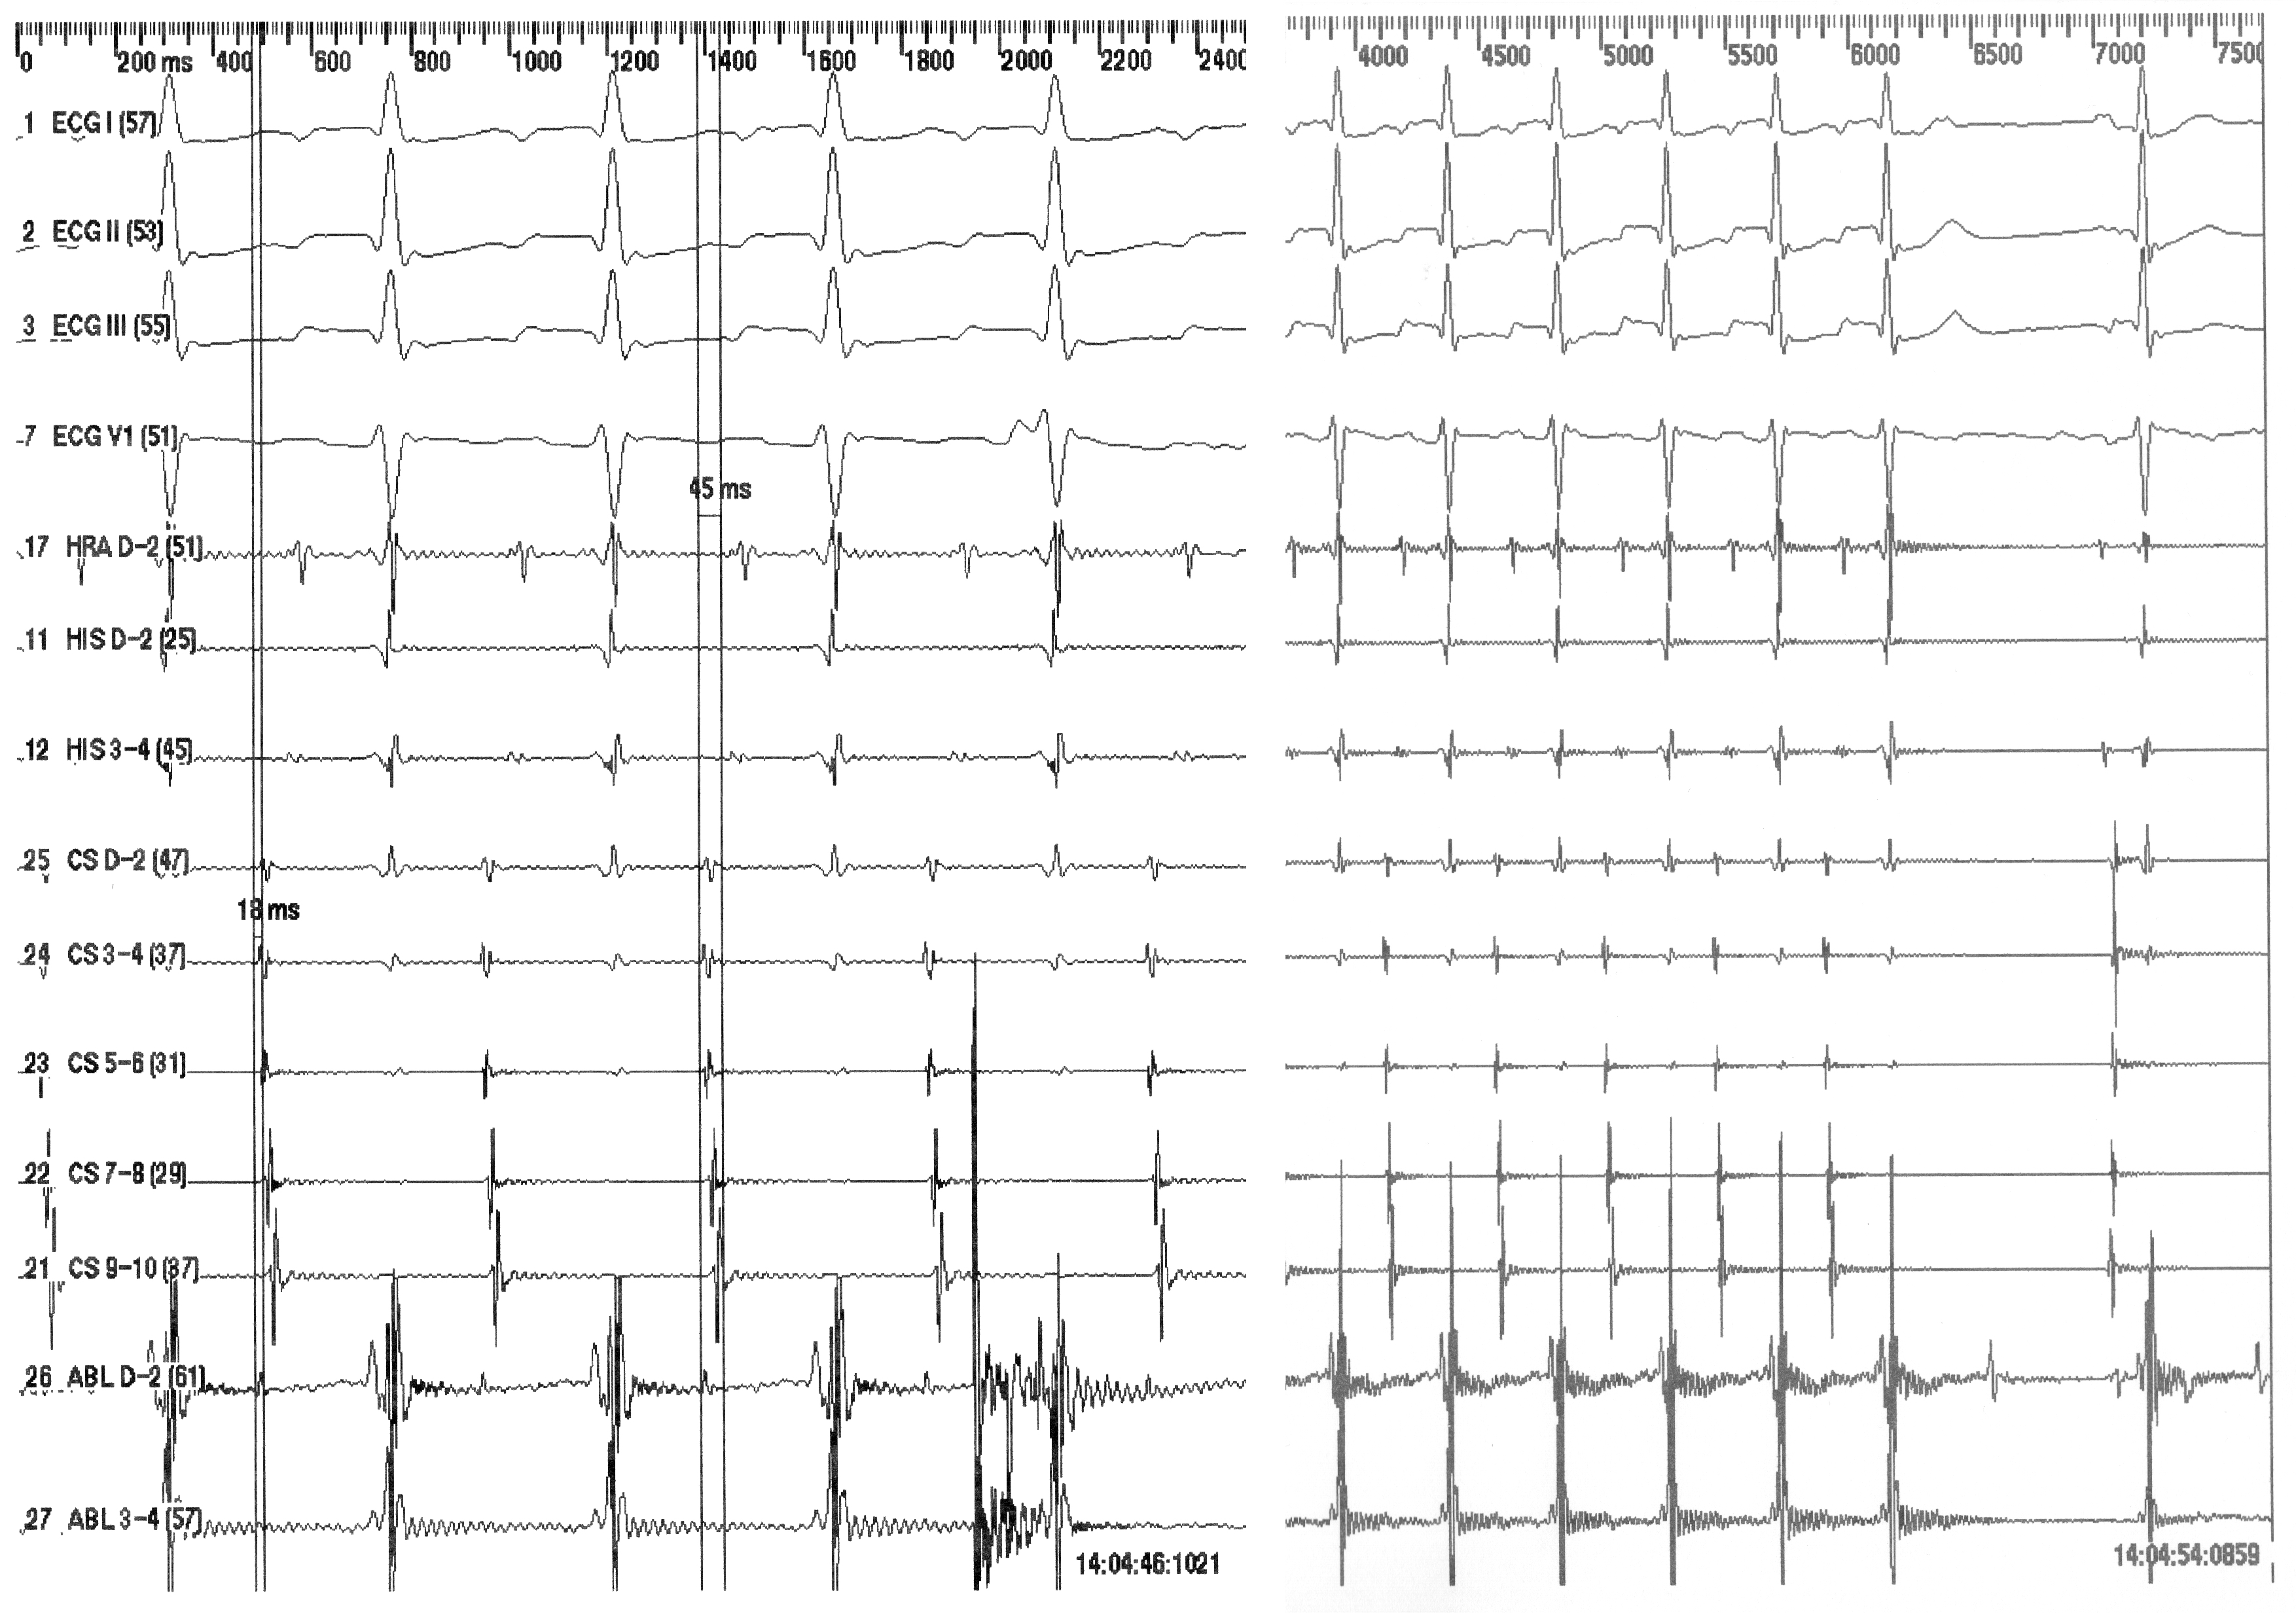

Permanent junctional reciprocating tachycardia (PJRT) is an uncommon form of supraventricular tachycardia due to an accessory pathway with slow retrograde conduction that is mostly localized in the posteroseptal area. The standard ECG shows long RP tachycardia with negative P waves in the inferior leads and positive P waves in leads I and aVL. We report a case of PJRT in a 31-year-old lady with incessant long RP tachycardia displaying negative P waves not only in the inferior leads but also in leads I and aVL. The accessory pathway was localized in the left posteroseptal region and managed successfully with radiofrequency catheter ablation.